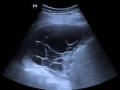

Chest ultrasound with multiloculated pleural effusion